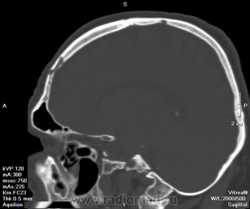

- https://radiomed.ru/sites/default/files/styles/case_slider_image/public/user/5821/1303118895.593.png?itok=Eic1AKYB

- https://radiomed.ru/sites/default/files/styles/case_slider_image/public/user/5821/1303118902.156.png?itok=pHc7od_7

- https://radiomed.ru/sites/default/files/styles/case_slider_image/public/user/5821/1303118910.250.png?itok=et1QTGXF

- https://radiomed.ru/sites/default/files/styles/case_slider_image/public/user/5821/1303118921.187.png?itok=SnhkGwSh

- https://radiomed.ru/sites/default/files/styles/case_slider_image/public/user/5821/1303118924.187.png?itok=_hTxi0xR

- https://radiomed.ru/sites/default/files/styles/case_slider_image/public/user/5821/1303118926.828.png?itok=V5geQffw

- https://radiomed.ru/sites/default/files/styles/case_slider_image/public/user/5821/1303118934.001.png?itok=lgI5vH_Y

Первая мысль была о гистиоцитозе Х. Клиника, цель исследования? Случайная ли находка?

Попробуйте посмотреть с разной толщиной среза, можно в MIP. Возможно это расширенные диплоические вены. Дефекты не на всю толщину кости, похоже только в диплоэ.

цель исследования ОНМК? на КТ дисциркуляторные очаги, ничего свежего. Находка случайная

Вены.